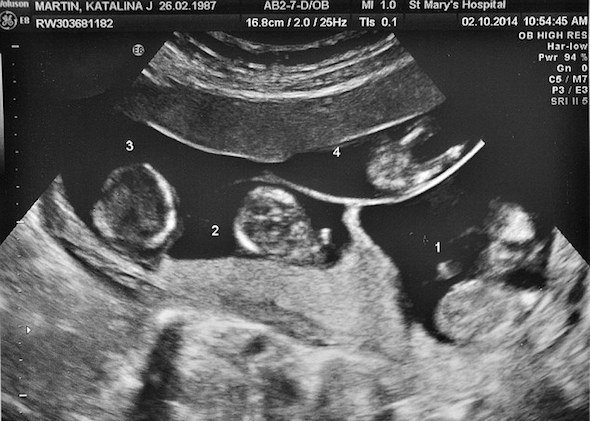

В семье Каталины Мартин (Katalina Martin) и Мэтью Дэвиса (Matthew Davis) из города Стокпорт (Британия) произошел уникальный случай: 28-летняя женщина родила «четверняшек» без помощи ЭКО.

2 мальчика и 2 девочки - близнецы Амелия, София, Астон и Роман - стали своеобразным национальным рекордом: каждый из них развился из самостоятельной оплодотворенной яйцеклетки. Дети появились на свет на 30-й неделе, их вес составлял от 1 300 до 1 670 граммов.

Этот редкий случай произошел в семье Каталины Мартин и Мэттью Дэвиса из города Стокпорт (Британия), которые начали жить вместе 2 года назад. Гражданские супруги зачали «четверню» после нескольких попыток.

Каталина зачала детей естественным путем, не прибегая к помощи ЭКО. По статистике, неидентичные близнецы в таких случаях рождаются не чаще чем 1 раз на 700 000 беременностей.

У пары есть дополнительный повод считать рождение «четверняшек» чудом: дело в том, что Каталина страдает поликистозом яичников, врачи предупреждали ее, что ее сын от первого брака может стать для женщины последним.